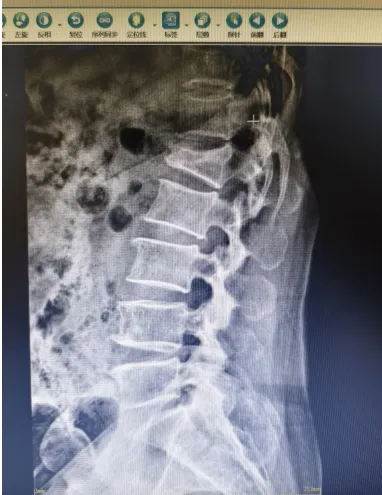

目前脊柱椎體成形手術(shù)是針對骨質(zhì)疏松所致的壓縮性骨折,椎體腫瘤等椎體壓縮性或病理性骨折所做的一種微創(chuàng)手術(shù)。椎體成形術(shù)對患者的疼痛緩解率較高,許多患者備受腰酸背痛的困擾,在手術(shù)后很快就感覺到疼痛的明顯緩解,手術(shù)在局麻下進(jìn)行,創(chuàng)傷小、安全性高,術(shù)后數(shù)小時(shí)即可下地活動,有效避免了術(shù)后可能發(fā)生的神志障礙,也避免了因長期臥床引起的褥瘡、肺炎等并發(fā)癥,尤其適合于老年患者。